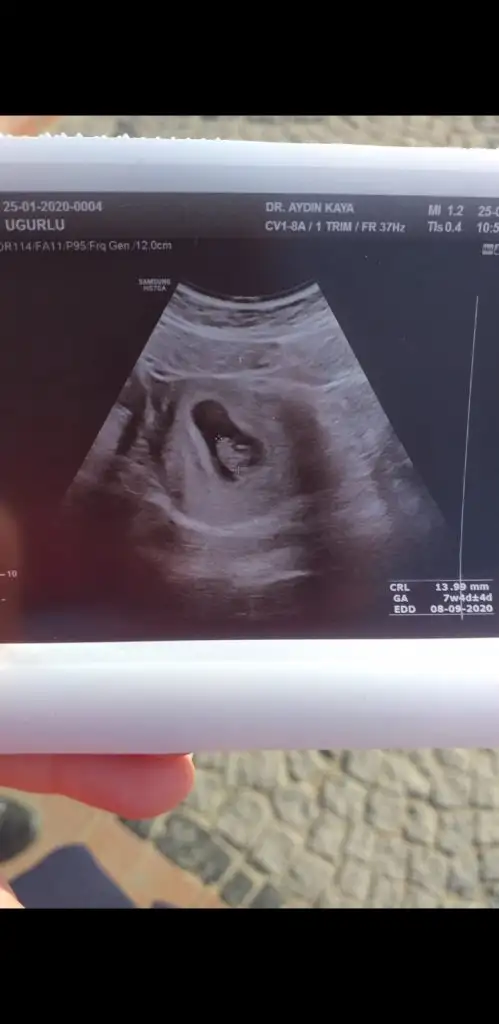

Benimkinde de bakar mısınız? 7 haftalıkİnşallah saglıkla gönlünüzdeki olur

Buna göre kız siz nub için 11 yada 12 hafta usg paylaşınSizce benimki nedir hanımlar? Karından usg ile bakıldıIkra meyra

TesekkurlerBuna göre kız siz nub için 11 yada 12 hafta usg paylaşın